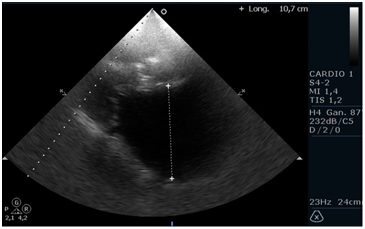

Patient of 75 years, height 165 cm and weight 72kg, with a history of mitral valve disease secondary to Rheumatic Fever. Percutaneous valvuloplasty was performed with balloon (Tecnica de Inoue) 6 years ago. Found in permanent atrial fibrillation(AF), NYHA functional class II, medicated with acenocoumarol, enalapril 10mg 2times/day, carvedilol 6.25mg 2times/day, spironolactone 25mg/day, furosemide 20mg/day and rosuvastatin 20mg/day. A Doppler echocardiogram is requested for dyspnea. It highlights the great biatrial dilatation to left predominance with moderate to severe mitral regurgitation, thickened mitral valve with characteristic stiffness (anterior valve in hockey stick), mitral stenosis moderated to severe by hemipresion time (THP) with an average of 10 beats (per to be found in atrial fibrillation rhythm) and systolic pressure in the pulmonary artery of 47mmHg. Left ventricular systolic function preserved. The left atrium measures 10.7cm in the anterior-posterior direction, an area in 4 chambers of 109 cm and an area in 2 chambers of 102cm2, obtaining a volume by the biplane method of 778ml (428ml/m2), remarking that currently the normal area by echocardiography is less than 34ml/m2.1 He presented with upper gastrointestinal bleeding with third episode of significant bleeding in 2 months that required blood transfusion due to gastric and duodenal ulceration. Mitral valve replacement is proposed with biological prosthesis, reduction of atrial volume, closure of left atrial appendage and isolation of pulmonary veins (Figure 1-3).

Figure 1 plane echocardiographic paraesternal long axis observing thickening and restriction of opening of the mitral valve and anteroposterior diameter of the left atrium increased (10.7 cm)